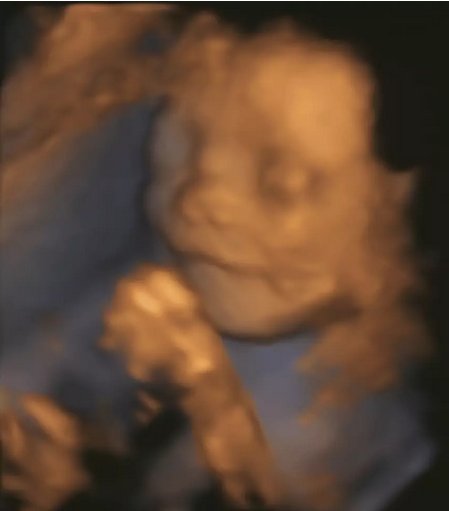

“我是从哪里来的?”他(她)爸他(她)妈,你该如何回答

“我是从哪里来的?”

面对这令爸妈十分尴尬的问题

你该如何回答?

生命,从何而来

颗小小的细胞

历经了什么样的过程

逐渐成长至个完整的生命体

......